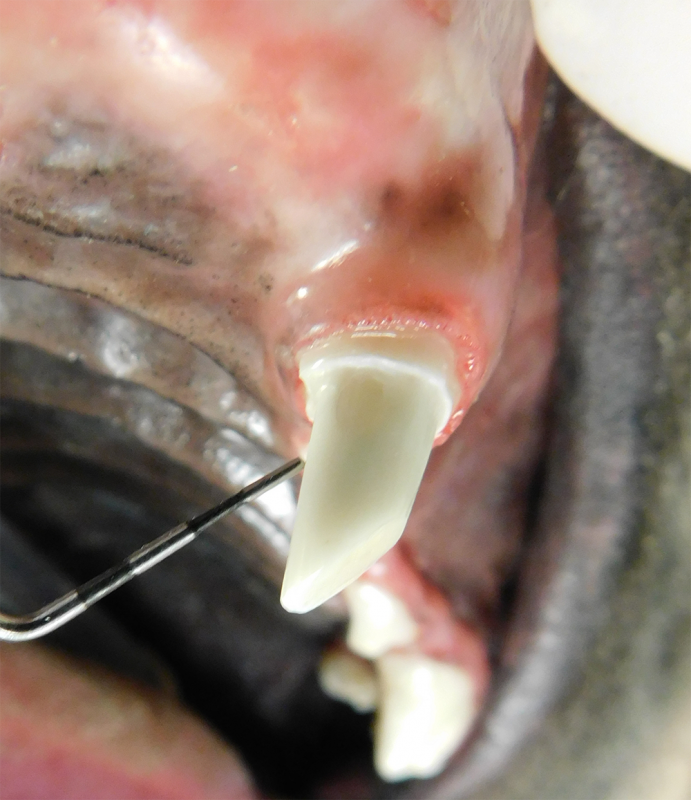

Root Canal Therapy

Root canal therapy is an excellent option for saving important teeth that have been fractured or are determined to be non-vital. The procedure is performed exactly as it would be for a human, except your pet will be dreaming peacefully under anesthesia. In many cases, root canal therapy is much easier on your pet than extraction, and preserves the structure of the tooth. It is important to have the root canal x-rayed periodically to monitor for any problems.